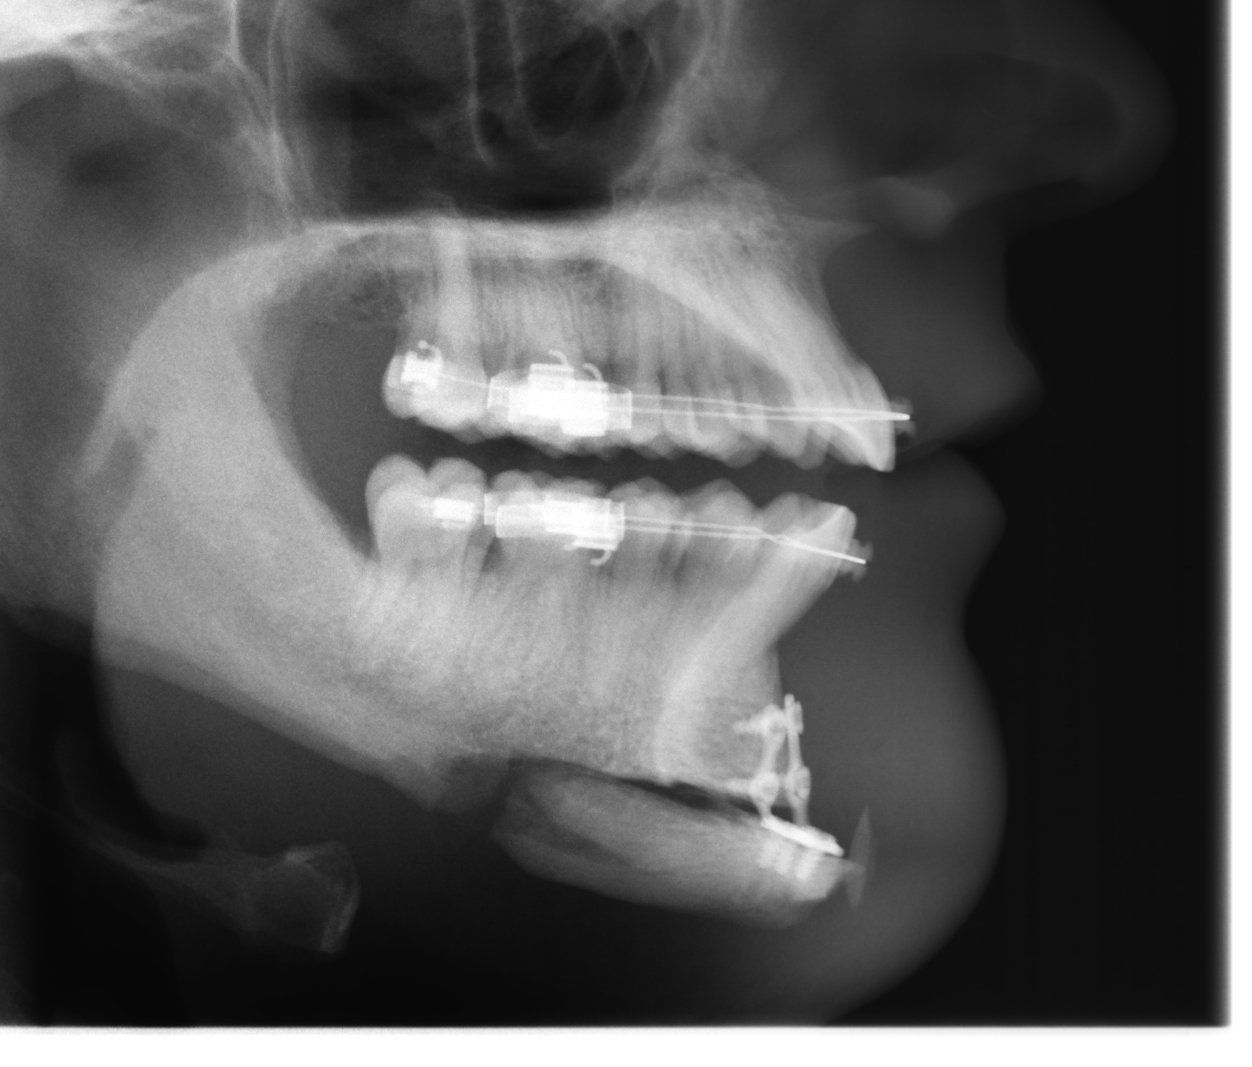

The Chinoplasty

Planning and implementation of a chin plastic as a download

Own bone can be sawed, moved and removed. Plastic can be introduced and exchanged. Access is through the gum line incision. The operation is usually performed under anesthesia. The cost of the operation including anesthesia and VAT is €1,799.00.